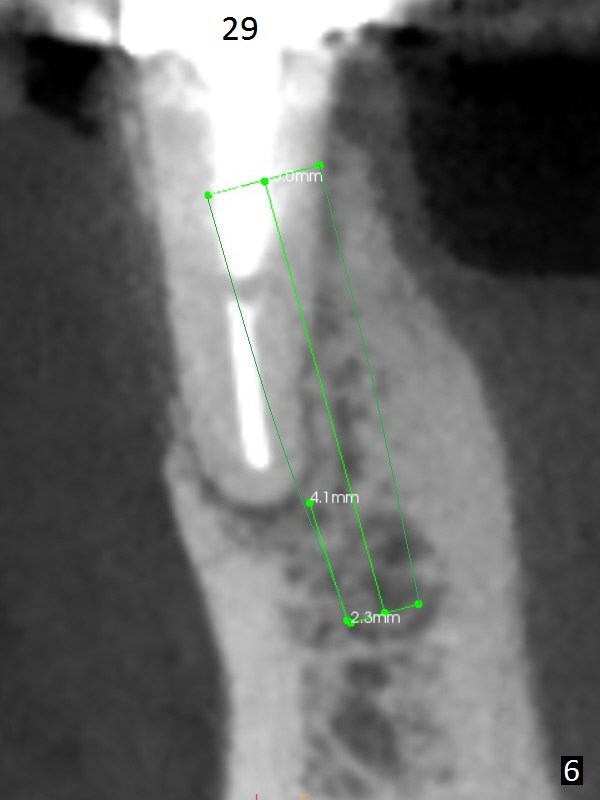

A 50-year-old man has pain and swelling buccal to the tooth #29 with large distal radiolucency (Fig.1 *).  The bridge will be sectioned between #30 and 31.  The mesial segment of the bridge is expected to separate from #29 post space; the mesial abutment is presumed to have vertical fracture (Fig.4 red line or root perforation due to oversized post (>)).  After intraligamental injection, extraction and no Antibiotic treatment, a narrow long implant (Fig.6,7: 3.8x15 or 13 mm) will be placed as mesial and lingual as possible to avoid the buccal bony defect (Fig.5 >; repaired with Osteotape or PRF membrane) and the Mental Loop (Fig.1 >).